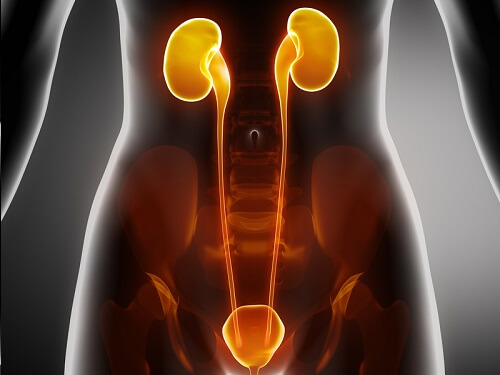

Leia também os melhores conselhos para cuidar de seus rins

4. Infecção nas vias urinárias

Nem todas as causas de dor lombar são produto de uma condição na coluna, nos nervos ou nos músculos. Também pode ser devido a um problema em um órgão localizado na área da pelve.

Uma das causas mais comuns da lombalgia são infecções do trato urinário. O que acontece é que se houver um problema nos rins, a área ficará inflamada e causará desconforto.